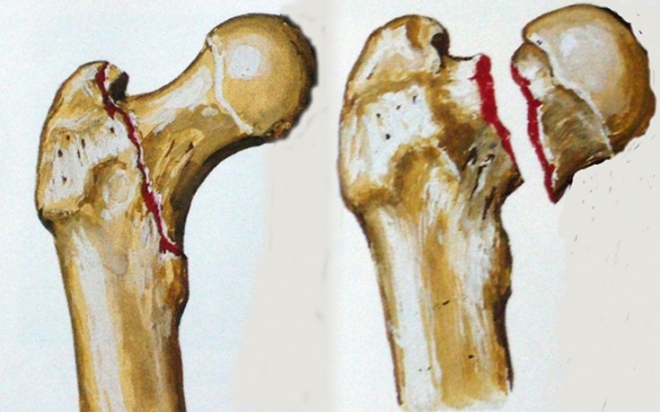

Τα κατάγματα του ισχίου ανάλογα με το σημείο του οστού που συμβαίνουν χωρίζονται αδρά σε διατροχαντήρια και υποκεφαλικά.